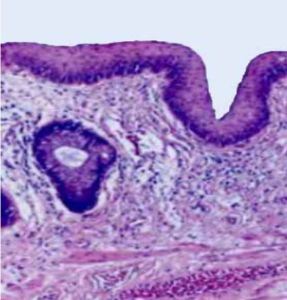

The external anal margin is generally thicker and drier compared to the rest of the perianal skin

This area has a tougher skin texture, which helps protect it from friction and abrasion